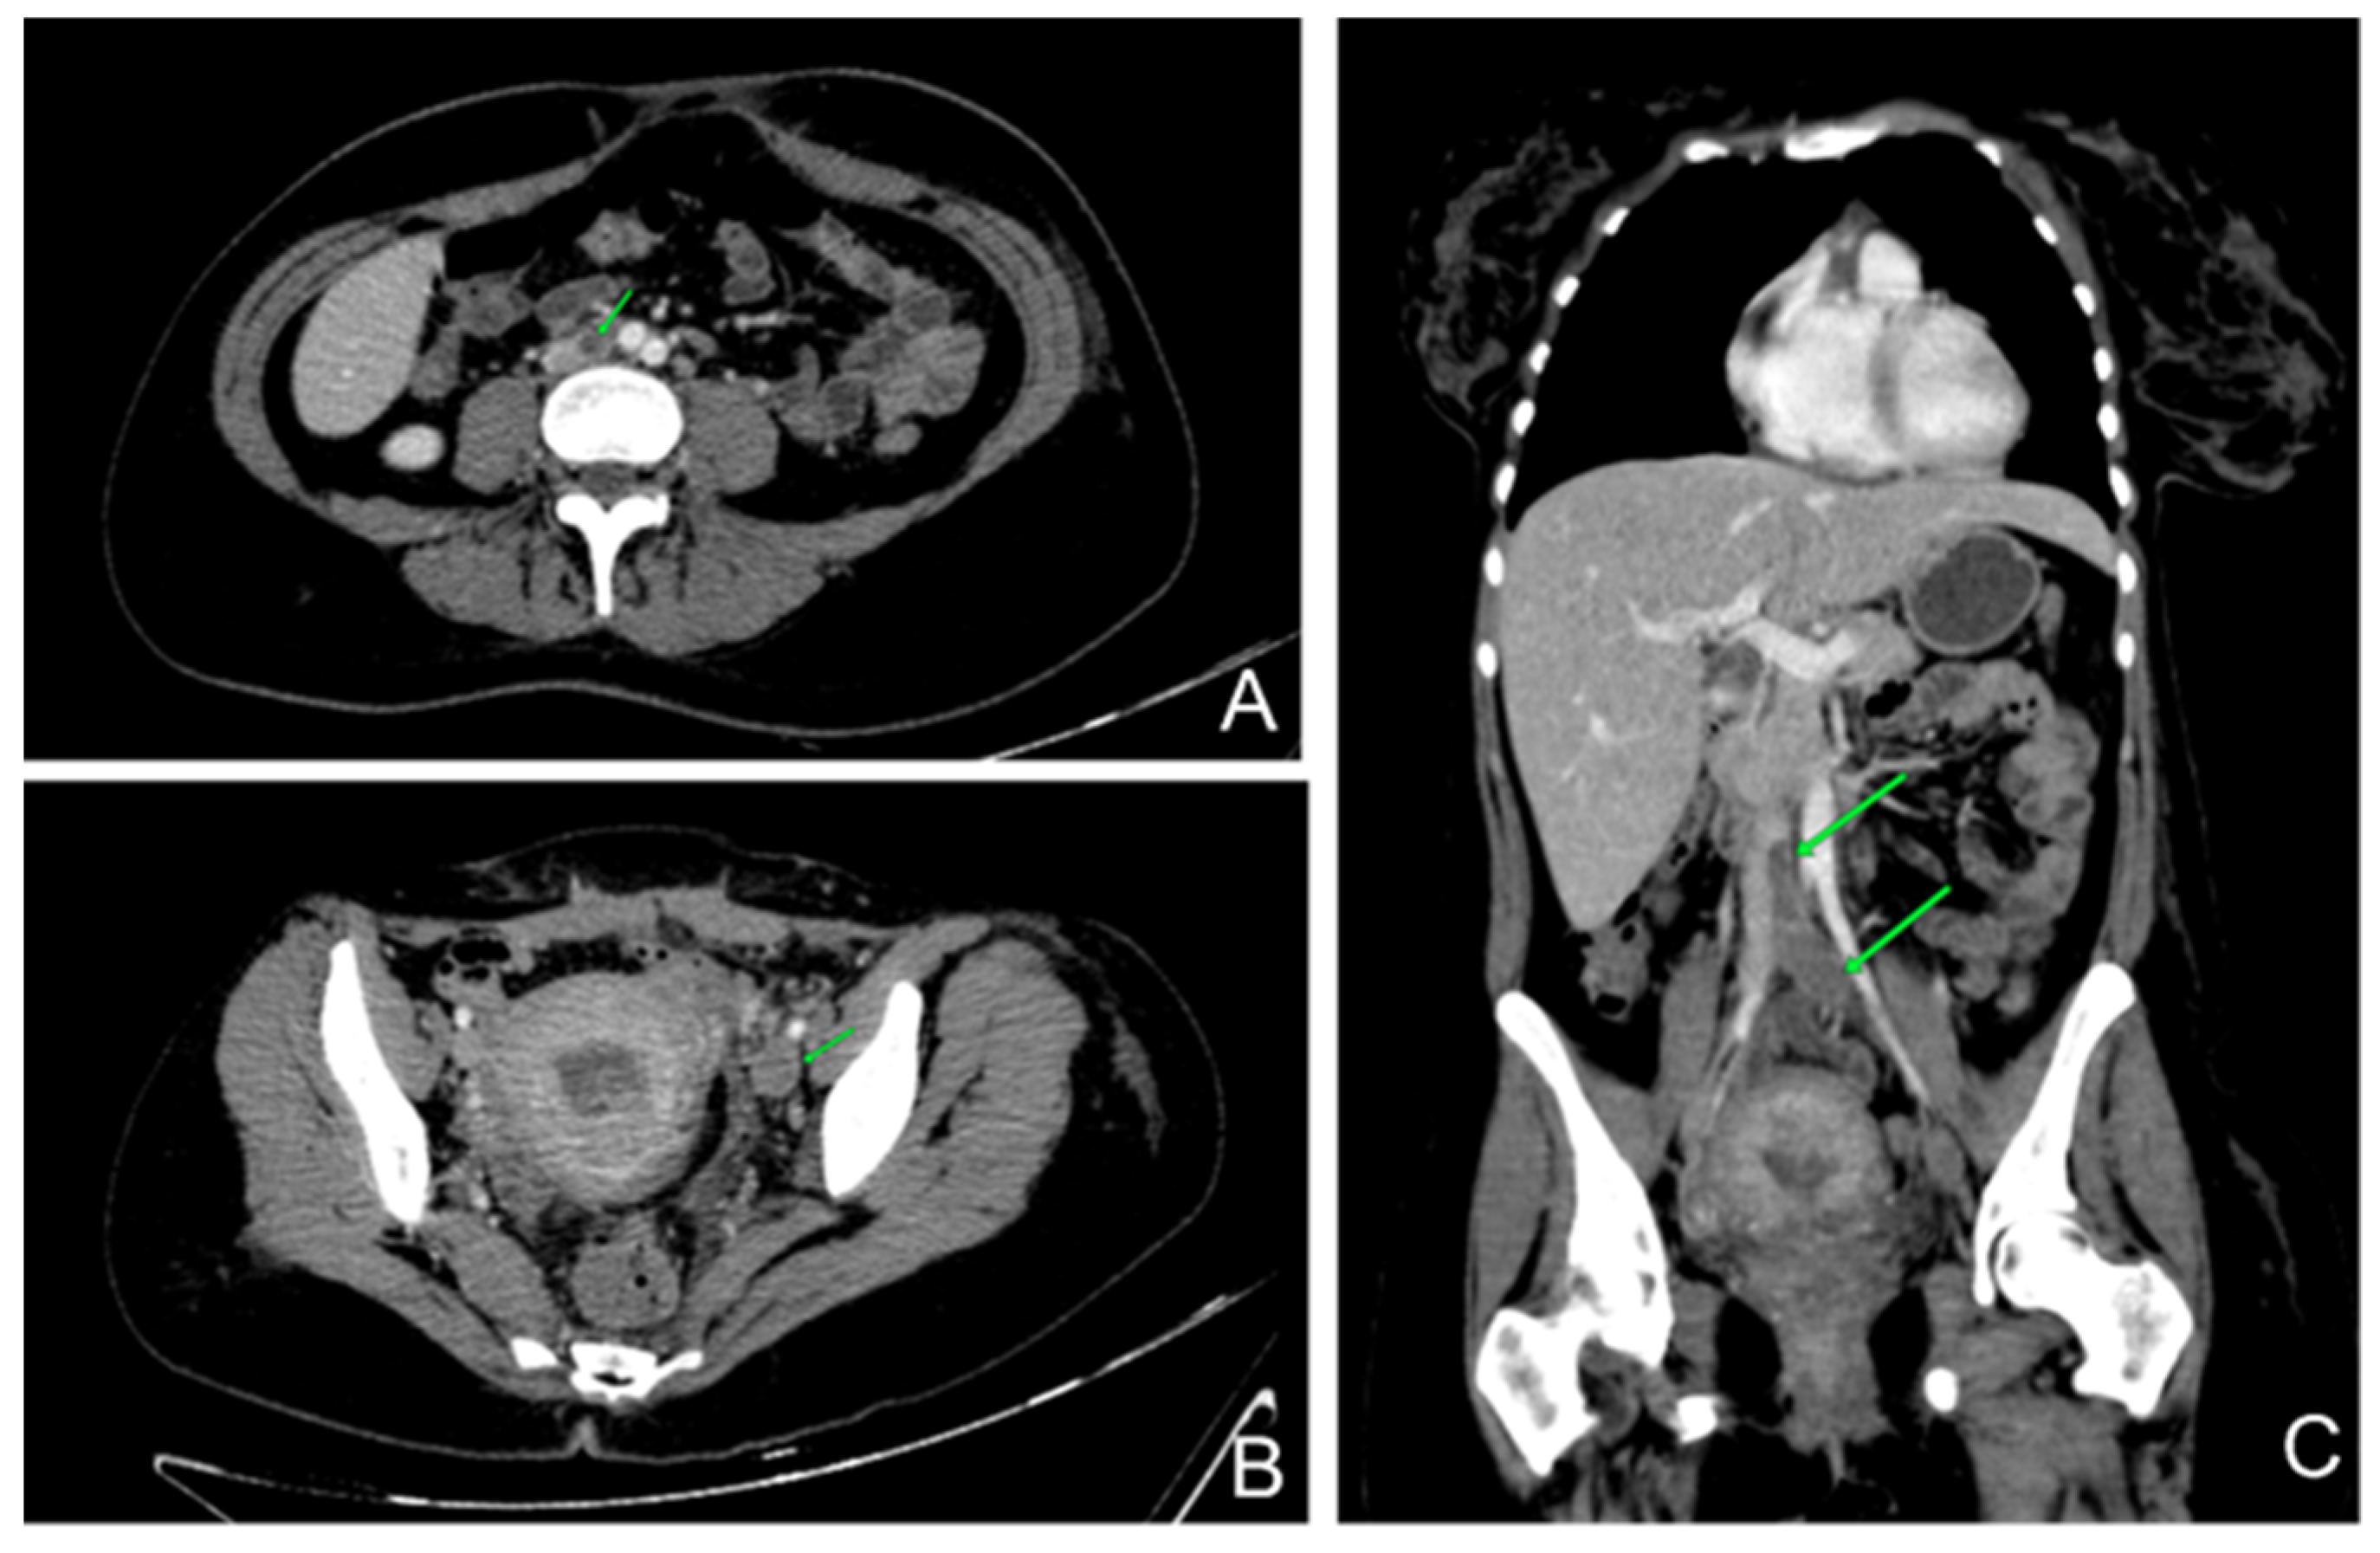

After six days under heparin treatment with therapeutic dose, she started to complain of interscapular pain and dyspnea with slight oxygen desaturation (SpO2 94%). She immediately underwent a chest–abdomen–pelvis contrast-enhanced CT that revealed moderate pulmonary embolism and a left inferior vena cava thrombosis (Figure 2). Having a high risk of cerebral bleeding and extensive deep vein thrombosis, the placement of a filter on the inferior vena cava was considered.

Figure 2. Contrast-enhanced thorax abdominal and pelvis CT: (A)—axial abdominal CT shows thrombus in inferior vena cava; (B)—axial pelvis CT reveals the extension of the thrombus in the left external iliac vein; (C)—coronal CT encompasses the length of the thrombus.